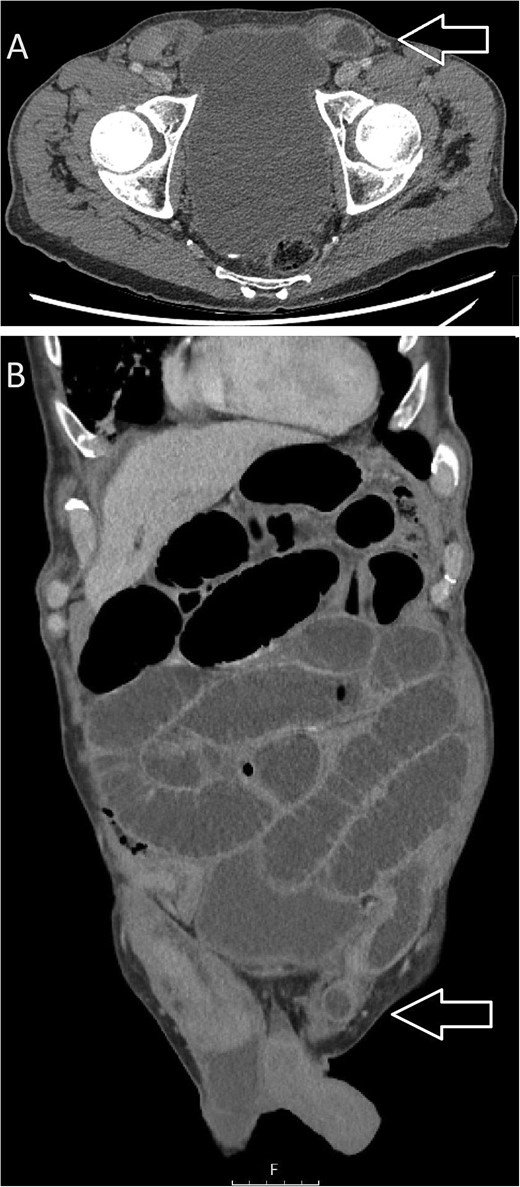

Computed tomography (CT) of the abdomen and pelvis revealed significant dilatation of the small bowel loops, measuring up to 40 mm in diameter, with a sharp transition point at the site of the left inguinal hernia, suggesting small bowel obstruction due to an obstructed, incarcerated left inguinal hernia (see Fig. 1). The CT also identified early pneumonia in the lung bases bilaterally.

CT images: (A) axial and (B) coronal views suggestive of small bowel obstruction secondary to an obstructed, incarcerated left inguinal hernia. Arrows have been added to the image to mark the site of the left inguinal hernia.